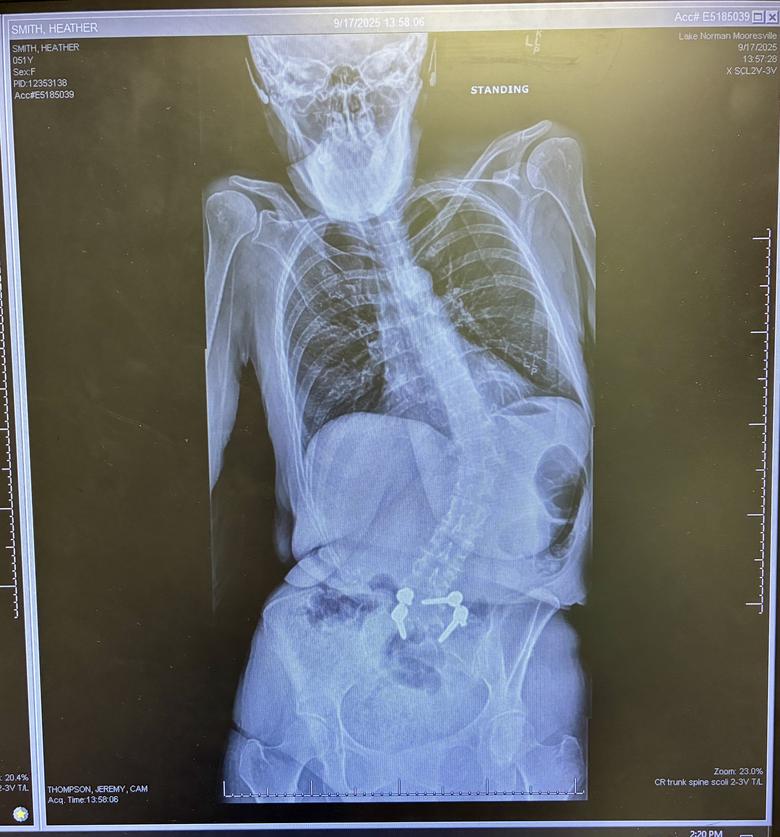

Everyone, I owe each and all of you a huge apology for just now getting back to you. Roughly 2 months ago, which was when I stopped posting, I started having very bad issues with my left hand which was later determined to be “trigger finger” on both my middle and ring fingers. It got to the point where those fingers were locking up on me and to move them from their position felt like I was trying to break them . I had literally lost the use of my left hand. Well last week, I had surgery on my hand to free up the tendons in my palm to prevent that from happening anymore. (*THE FOLLOWING VIDEO IS GRAPHIC!!*)https://vimeo.com/manage/videos/1130619627 ![]() ![]() However, I’m now bruised from the front side of my palm, to the back side of my palm, and basically feel like I’m constantly grabbing long needle cactus plants right where they cut me open 🫣 ![]() . ![]() ![]() I will have to keep bandages on it for 2 weeks straight (which you never realize how many things you depend on *2* hands for until you only have one!). I have been so reluctant to handle anyone’s books as I have been dropping things left and right. 🤦🏻♀️ . I’ve been petrified that I would damage something. But as soon as I get the bandages off and the use of my hand back, I’ll be able to start packing up books. I do have an update on my back, and it’s not good…it’s not good at all. I had new images taken, and these were the results: ![]() ![]() I started crying when I saw them. As you can see, my spine has collapsed much worse both sideways and forwards in just the past 2-3 years since my last imaging was taken. What’s worse, I’ve now been told that at best, I have perhaps another 7-8 years before I won’t be able to walk anymore (that’s assuming that the catastrophic heart failure side of Emery-Driefuss Muscular Dystrophy doesn’t get me first…and is it so wrong to kinda be rooting for that outcome?). Guys, every day I lose a little bit more will to keep going. I’m sorry, I really did just want to let everyone know what had been going on. But on a brighter note…I’ve set aside a bunch more books and slabs to sell if anyone is interested. Lord knows I won’t be needing them . |